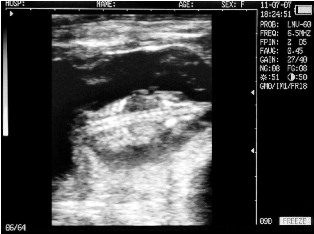

Ultrasound images of cows reproductive system, generated by a scanner Sonovet with rectal linear transducer.

Endometritis in the uterus of the cow